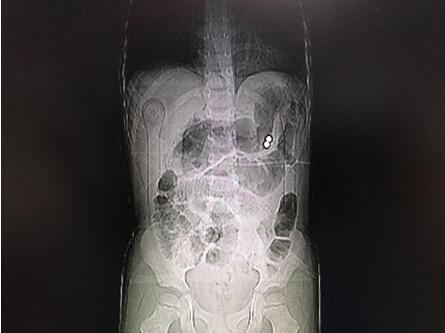

通訊員唐水平報道:近日,市中心醫(yī)院華新普外科收治了一位4歲的腹痛患兒,進(jìn)院后檢查發(fā)現(xiàn)腹腔內(nèi)有金屬異物及膈下游離氣體、腹腔積液,診斷為消化道穿孔并彌漫性腹膜炎。

據(jù)患兒監(jiān)護(hù)人講述,患兒平時喜好磁力玩具,發(fā)病前兩天曾先后誤兩顆服彩色磁力珠。由于磁力珠在胃腸道蠕動下移到不同部位,因其強(qiáng)大的吸力使間隔胃腸壁及橫結(jié)腸系膜相吸在一起,造成局部組織缺血,繼而壞死穿孔的嚴(yán)重后果。

經(jīng)手術(shù)探查發(fā)現(xiàn)胃體近大彎側(cè)、曲式韌帶下方8cm處空腸及橫結(jié)腸系膜各有一0.5cm大小穿孔,在胃穿孔處的胃腔內(nèi)外各發(fā)現(xiàn)一彩色磁力珠。經(jīng)修補(bǔ)胃腸道穿孔及抗感染、補(bǔ)液治療,患兒術(shù)后順利康復(fù)院。